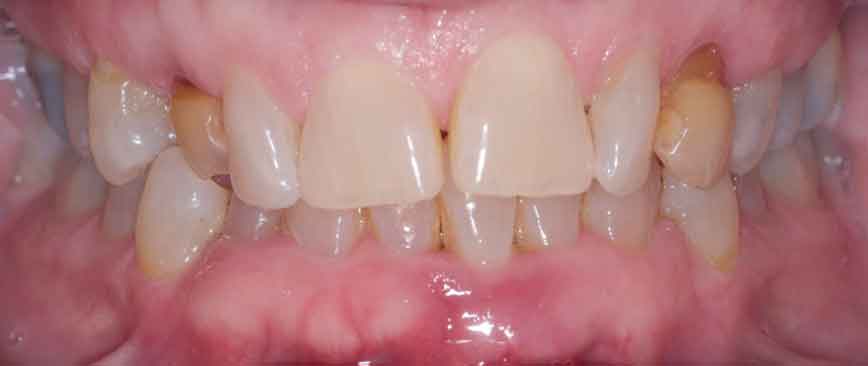

Return to "Modern Applications for The Cantilever Fixed Partial Denture" partial-denture-1 Next Previous